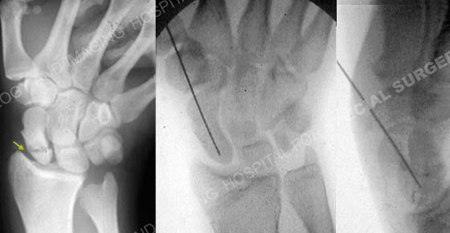

Anteroposterior (AP) radiograph (left image) revealing a scaphoid fracture and intraoperative fluoroscopic AP and lateral radiographic images (right images) illustrating reduction of the scaphoid fracture prior to placement of percutaneous screw fixation.